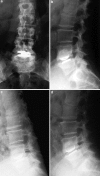

A retrospective clinical-radiological study to evaluate the long-term outcome after artificial disc replacement was performed. The objective is to investigate long-term results after implantation of a modular type artificial disc prosthesis in patients with degenerative disc disease (DDD). Total disc replacement (TDR) is a surgical procedure intended to save segmental spinal function, and thus replace spondylodesis. Short-term results are promising, whereas long-term results are scarce. The Charité TDR is the oldest existing implant, therefore, the longest possible follow-up is presented here. Seventy-one patients were treated with 84 Charité TDRs types I-III. Indication for TDR was moderate to severe DDD. Fifty-three patients (63 TDRs) were available for long-term follow-up of 17 years. Evaluation included Oswestry disability index, visual analog scale, overall outcome score, plain and extension/flexion radiographs. Implantation of Charité TDR resulted in a 60% rate of spontaneous ankylosis after 17 years. No significant difference between the three types of prostheses was found concerning clinical outcome. Reoperation was necessary in 11% of patients. Although no adjacent segment degeneration was observed in the functional implants (17%), these patients were significantly less satisfied than those with spontaneous ankylosis. TDR, nowadays, is an approved procedure. Proof that long-term results of TDR implantation in DDD are at least as good as fusion results is still missing.